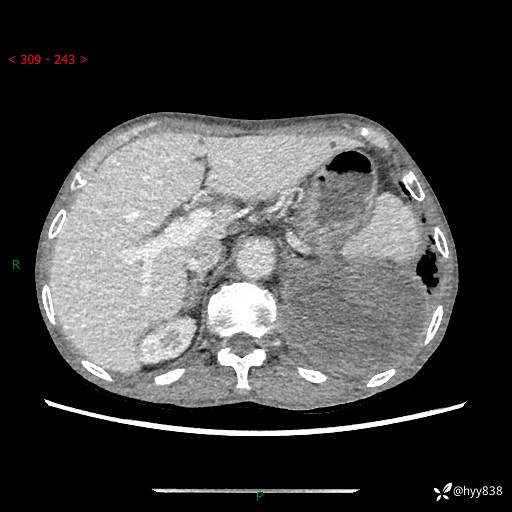

77岁/男,腹痛2月,CT发现左肺占位1天。巨大肿块,肺内或肺外来源…结果公布~

主诉:腹痛2月,CT发现左肺占位1天

现病史:患者于2025年9月间断左下腹胀痛,在当地镇卫生院行彩超检查考虑泌尿系结石,行止痛排石对症治疗未见明显好转;1天前腹痛症状加重,至当地市第三人民医院行CT检查:左肺下叶巨大团块状软组织影,考虑肿瘤性病变,建议增强CT检查;左侧胸腔积液;纵膈内淋巴结肿大;双肺肺气肿;右肺中叶纤维灶。为进一步求治,来我院就诊。

胸部CT平扫+增强